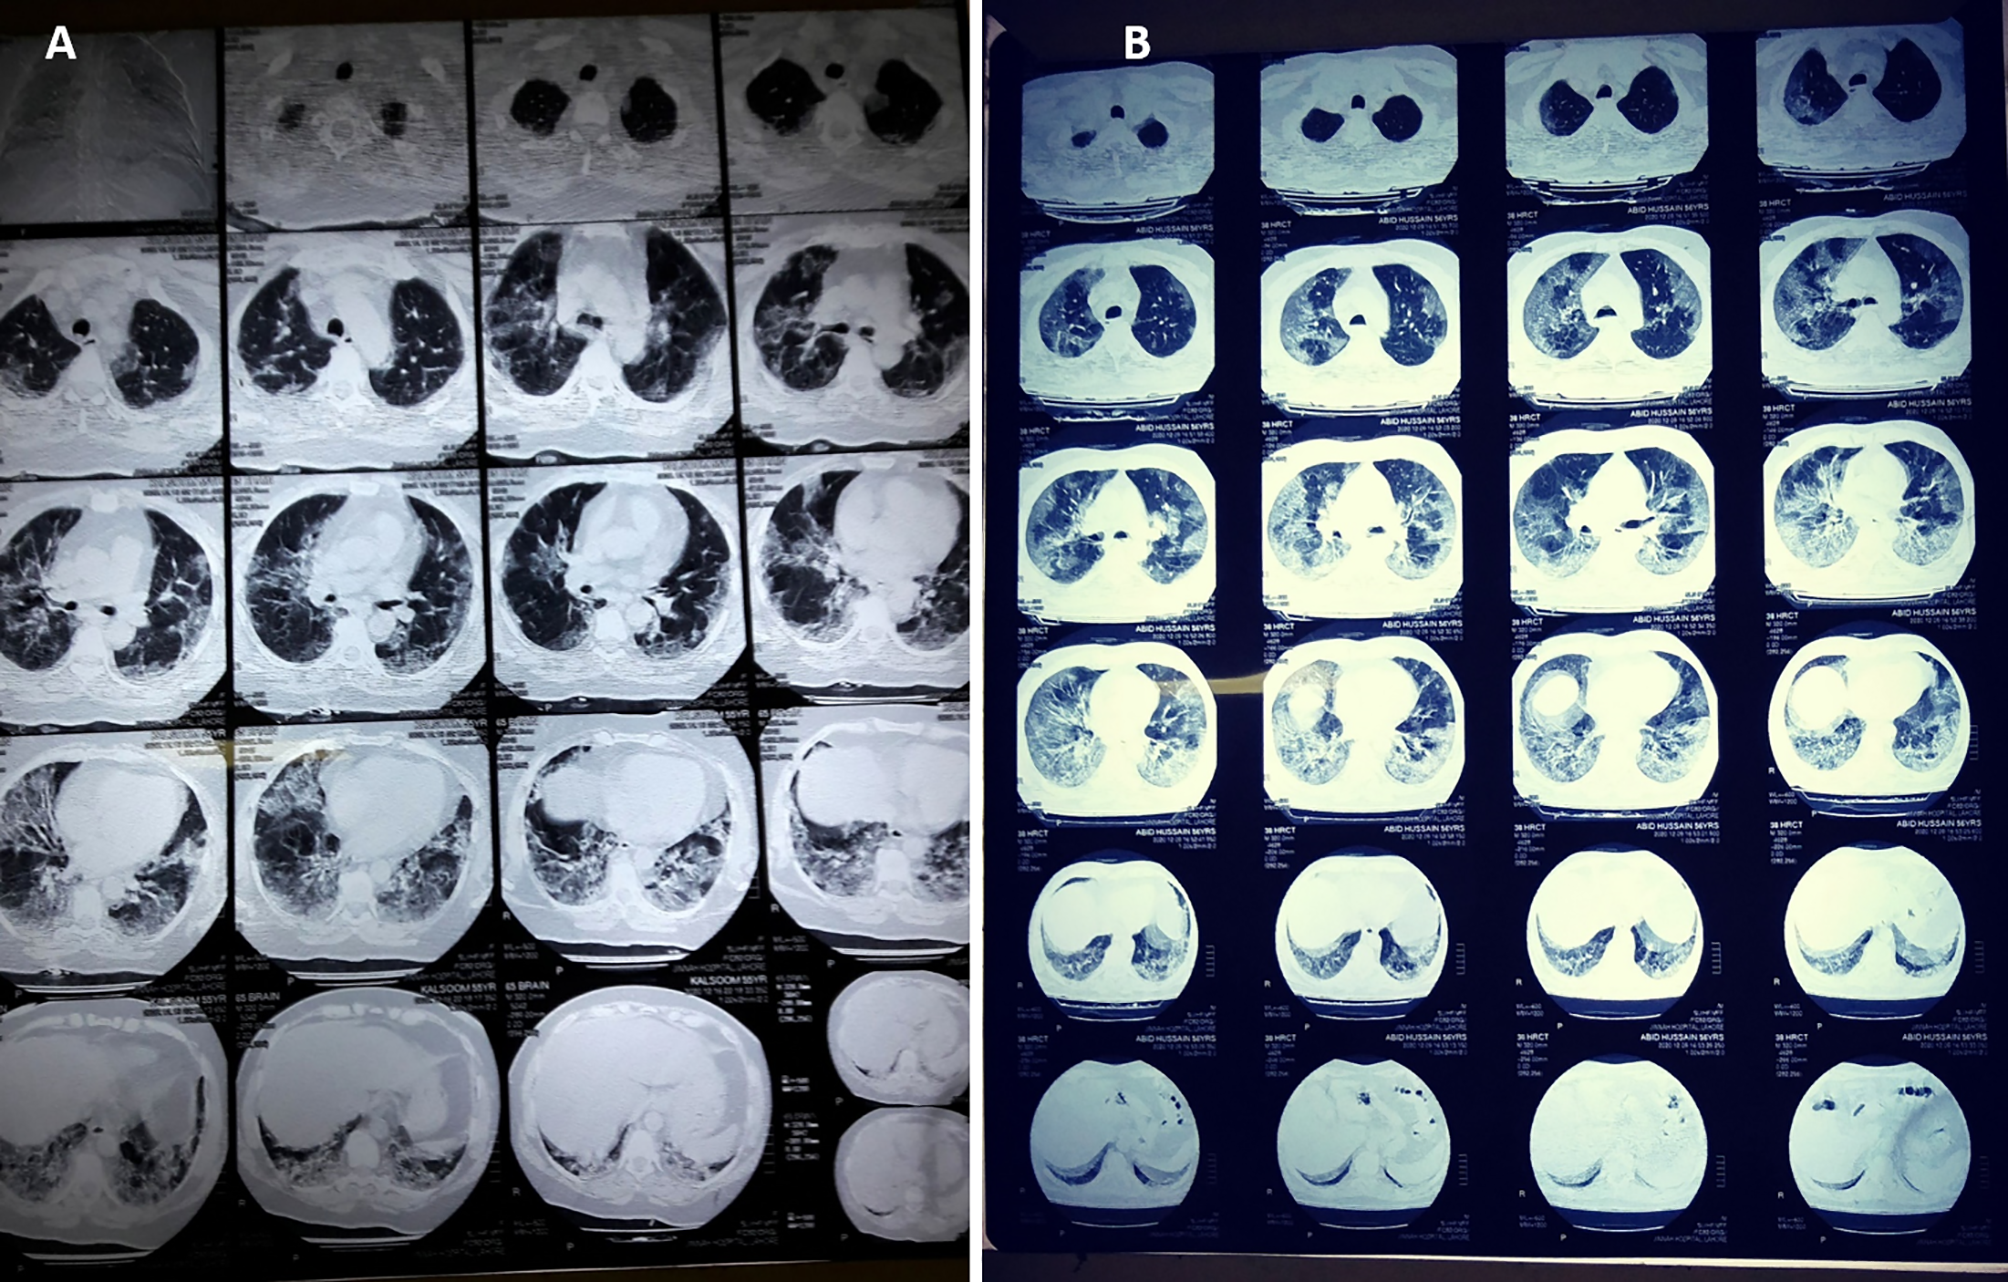

The patients who underwent chest CT scans were also assessed in this study, and the details are summarized in Table 7 and Figure 2. The mean age of these patients was 57 ± 12.6 years, including 76.7% male patients and 23.3% females. The mean percentage of lung involvement in male patients was 51.3 ± 15.8), and it was 54.3 ± 14.3 in female patients. Only 20% of the patients had age ≤50 years (38.3 ± 7.7), while a high number of patients (80%) had age of >50 years (62.4 ± 8.1). The most common findings were ground glass opacity (GGO; n = 28, 93.3%), mixed pattern of consolidation (n = 12, 40%), and interlobular septal thickening (n = 6, 20%). A small percentage of patients had GGO and opacities (n = 2, 6.7%), infiltration (n = 2, 6.7%), consolidation (n = 1, 3.3%) and cavitation (n = 1, 3.3%). Seventeen (57.7%) had five affected lobes, 8 (26.7%) had four affected lobes, 2 (6.7%) had three affected lobes, 2 (6.7%) had two affected lobes, and 1 (3.3%) had one affected lobe Figure 2.

Figure 2

CT scan digital images of (A) mild-to-moderate and (B) severe SARS-CoV-2-infected patients. The percentage of lung involvement can be spotted significantly in both types of patient.

Non-enhanced chest CT is a vital component in the diagnosis of patients suspected of a COVID-19 infection (Korevaar et al., 2020; Pruis et al., 2020). The pattern of GGO, GGO, and consolidation and interlobular septal thickening was the most prominent finding among the infected patients of different age groups, gender, and severity. The pattern of the findings is somewhat similar to that described in related studies on severe acute respiratory syndrome (Bernheim et al., 2020; Pan et al., 2020; Wu et al., 2020). In critical patients, a honey-combing pattern, traction bronchiectasis, and interlobar pleural traction can be observed. A follow-up CT after 6 months may show fibrotic changes in such patients (Ginsburg and Klugman, 2020; Han et al., 2021). A combination RT-PCR analysis and chest CT scan increases the sensitivity and specificity of COVID-19 diagnosis to 88 and 100%, respectively (He et al., 2020b). The semi-quantitative CT Severity Score System helps in showing the extent of pulmonary involvement. These are as follows: